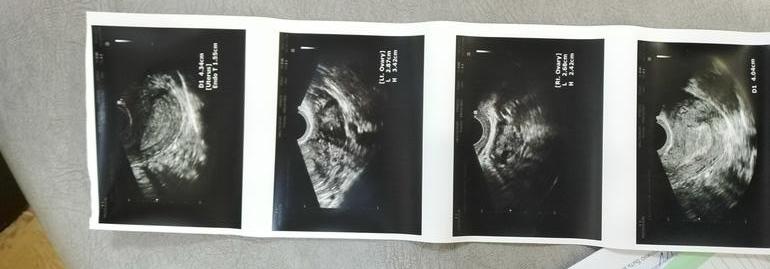

УЗИ на 25 дц.

Да, про ЖТ не написано, но ПЯ увеличен по сравнению с ЛЯ, наверное, там. Перед М оно вроде подсдувается, хотя на самом правом узи что-то похожее на ЖТ, но очень мелко и без заключения как-то трудно это предположить точно. Эндик шикарный, конечно. А тесты-то делали? Если есть Б, они уже будут полосатые.

Овуля была, про желтое не написала, эндометрий просто вау... Ждите.

Эндометрий я так понимаю 18мм? Я делала узи в том цикле на 20дц из 27дневного У меня был эндик 19мм,мне сказали что это гиперплазия

Вообще 18 это много, но для Б - в самый раз. Тут автор может с другими узи сравнить, если они были. Какой обычно эндик в первую фазу, какой во вторую. Тогда будет яснее.